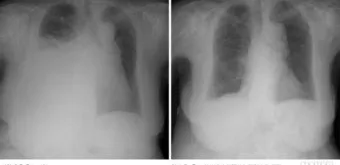

2단계, 흉부 X선 촬영입니다.

서서 찍은 단순 X선에서 보통 250mL 이상 흉수가 고이면 갈비뼈와 횡격막이 만나는 부분이 희미해지거나, 반달 모양의 음영이 보이기 시작한다고 알려져 있습니다.:contentReference[oaicite:21]{index=21}